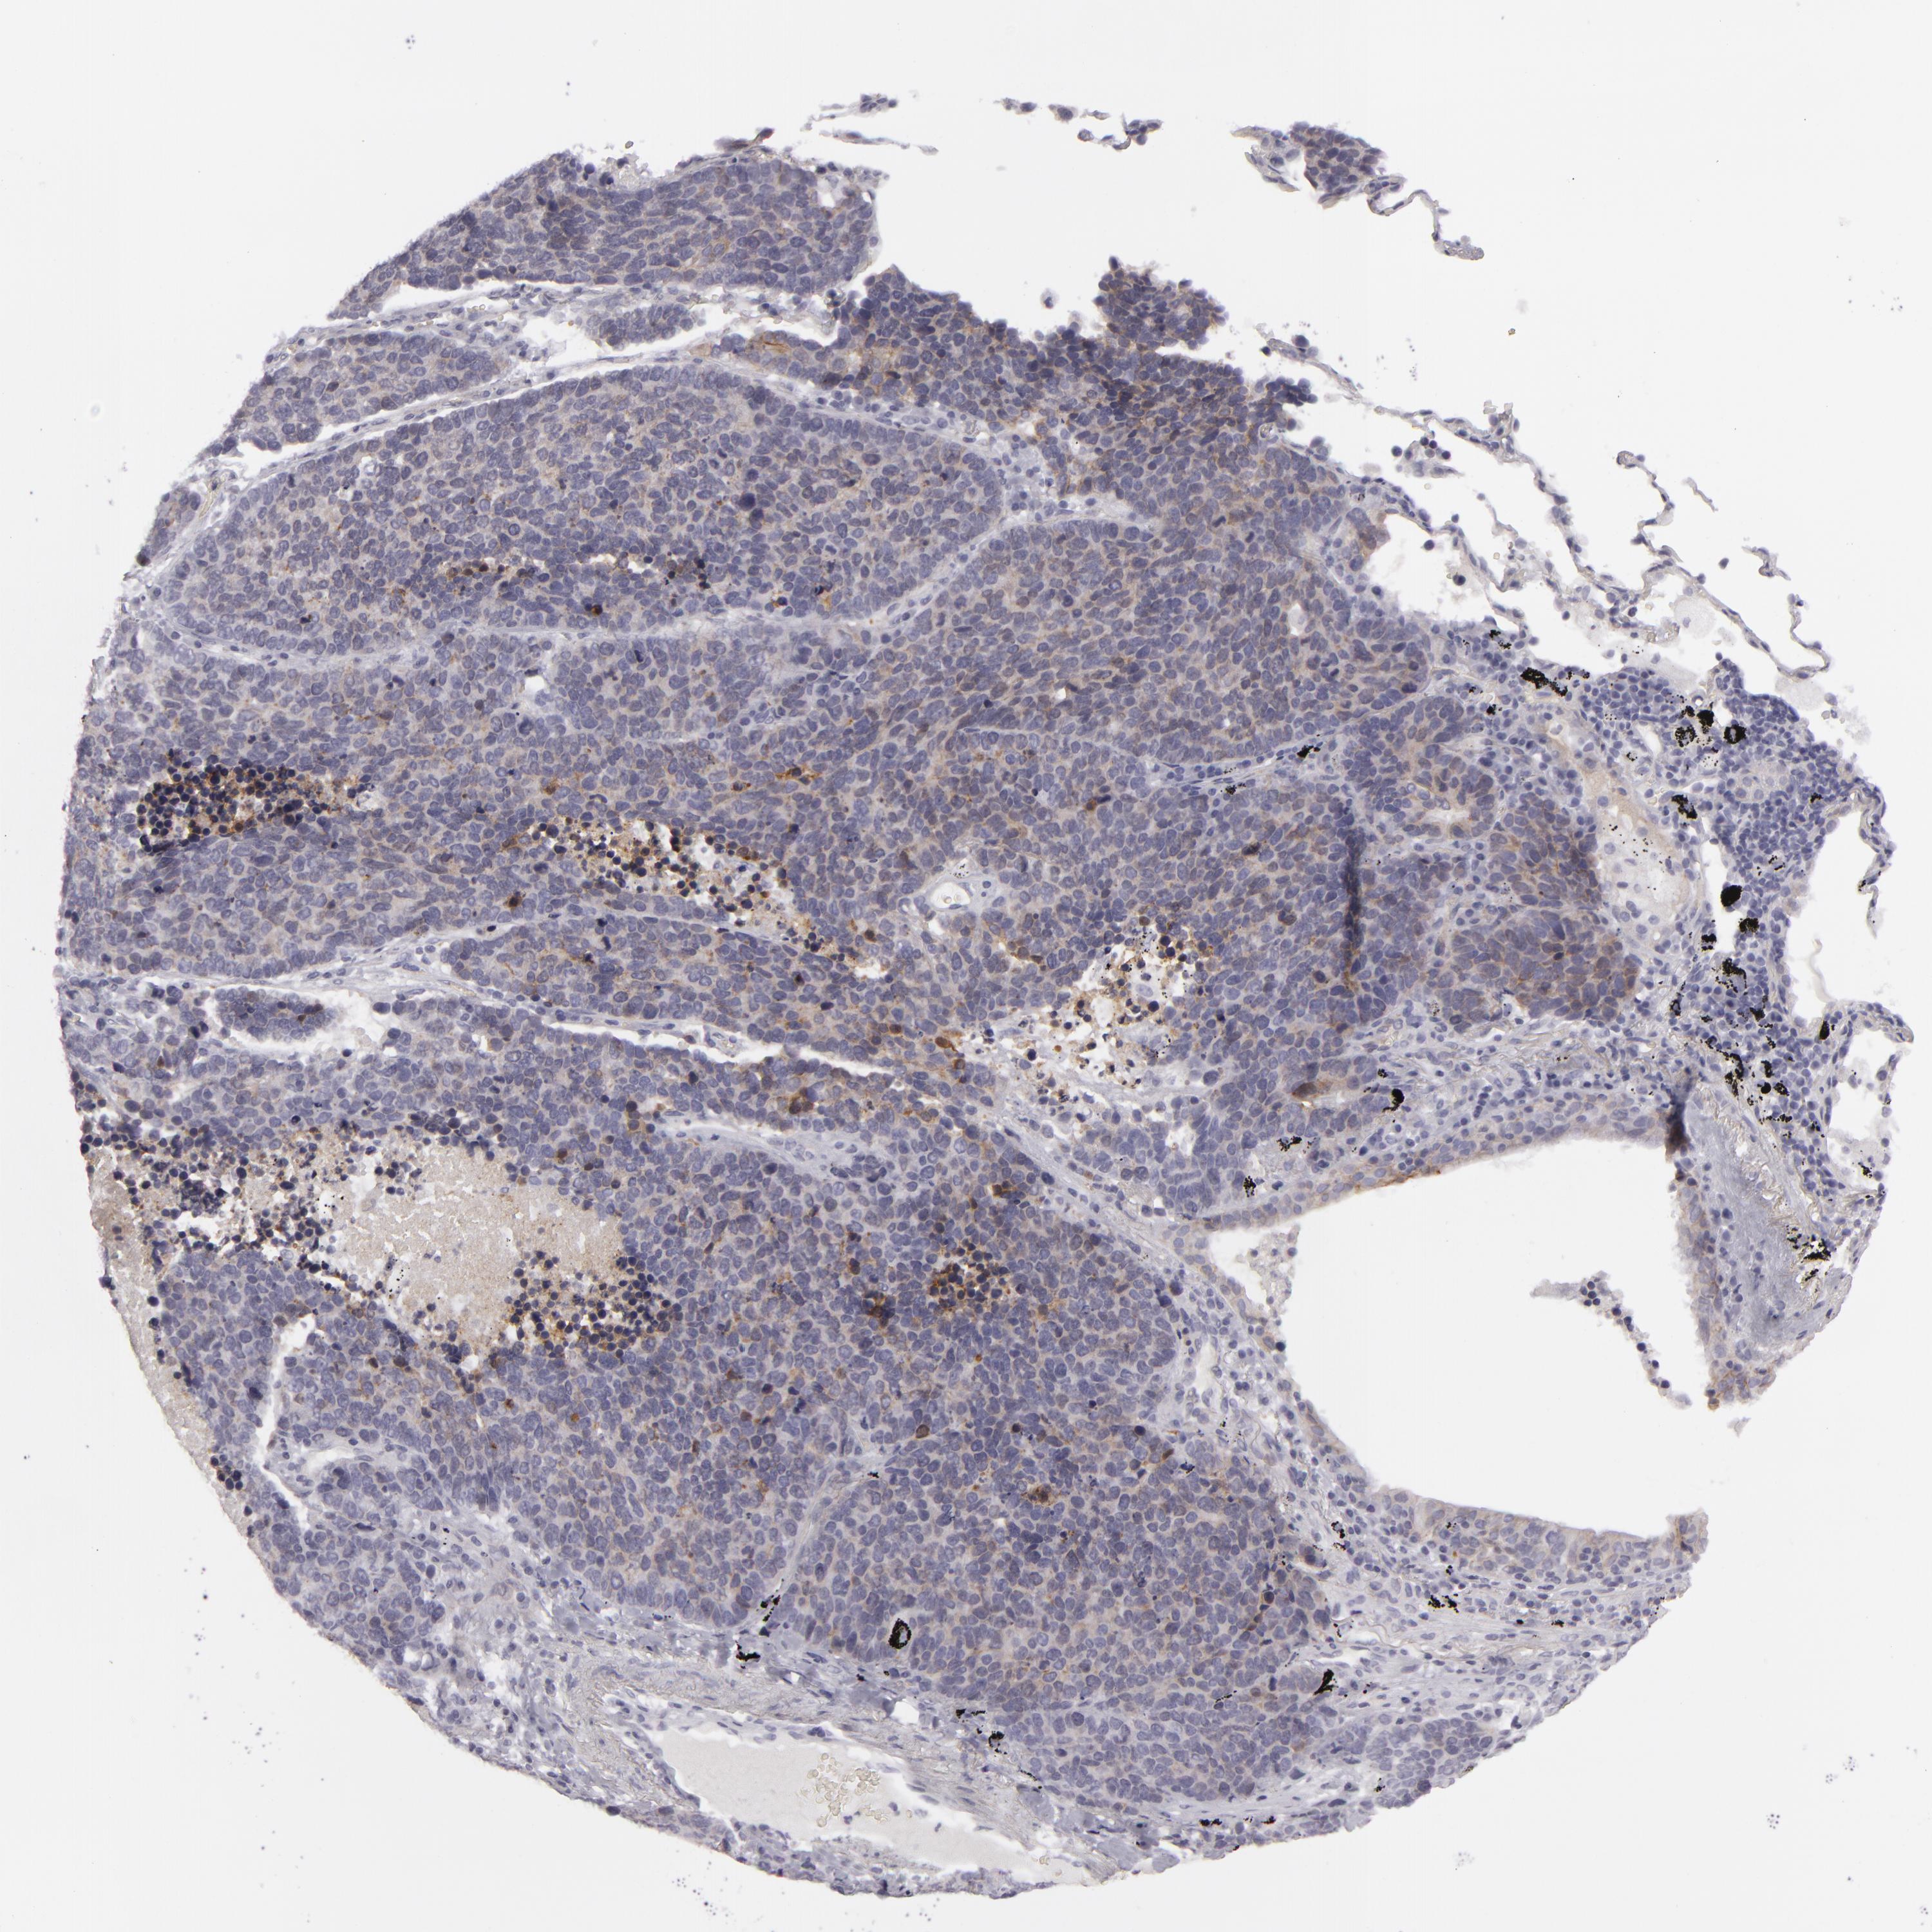

LUNG SQUAMOUS CELL CARCINOMA (TCGA) - Interactive survival scatter ploti

The Survival Scatter plot shows the clinical status (i.e. dead or alive) for all individuals in the patient cohort, based on the same data that underlies the corresponding Kaplan-Meier plots. Patients that are alive at last time for follow-up are shown in blue and patients who have died during the study are shown in red.

The x-axis shows the expression levels (FPKM) of the investigated gene in the tumor tissue at the time of diagnosis. The y-axis shows the follow-up time after diagnosis (years). Both axes are complimented with kernel density curves demonstrating the data density over the axes. The top density plot shows the expression levels (FPKM) distribution among dead (red) and alive patients (blue). The right density plot shows the data density of the survived years of dead patients with high and low expression levels respectively, stratified using the cutoff indicated by the vertical dashed line through the Survival Scatter plot. This cutoff is automatically defined based on the FPKM cutoff that minimizes the p-score. The cutoff can be changed by dragging the vertical line or by entering a cutoff value in the square labeled "Current cut-off".

Under the Survival Scatter plot the p-score landscape (black curve; left axis) is shown together with dead median separation (red curve; right axis). Dead median separation is the difference in median mRNA expression between patients who have died with high and low expression, respectively. It is calculated as follows: median FPKM expression of dead patients with high expression - median FPKM expression of dead patients with low expression. This is intended to aid the user in visually exploring custom cutoffs and the associated p-scores and dead median separation.

Individual patient data is displayed and can be filtered by clicking on one or more of the category buttons on the top of the page. Categories describing expression level and patient information include: high, low, alive, dead, female, male and tumor stages. The scale of the x-axis can be toggled between linear and log-scale by clicking on the "x log" button. Mouse-over function shows TCGA ID, patient information and mRNA expression (FPKM) for each patient.

& Survival analysisi

Kaplan-Meier plots summarize results from analysis of correlation between mRNA expression level and patient survival. Patients were divided based on level of expression into one of the two groups "low" (under cut off) or "high" (over cut off). X-axis shows time for survival (years) and y-axis shows the probability of survival, where 1.0 corresponds to 100 percent.

JUP is not prognostic in Lung Squamous Cell Carcinoma (TCGA)

Current cut offi

Current cut-off shows the cut-off (FPKM) currently selected. It may be changed manually. When the current cut-off is changed, the vertical dashed line indicating cut-off, the interactive survival scatter plot and the Kaplan-Meier curve will be automatically adjusted to show results accordingly.

:

Best expression cut offi

Based on the FPKM value of each gene, patients were classified into two groups and association between prognosis (survival) and gene expression (FPKM) was examined. The best expression cut-off refers the FPKM value that yields maximal difference with regard to survival between the two groups at the lowest log-rank P-value. Best expression cut-off was selected based on survival analysis .

When clicking on this number, the vertical dashed line indicating cut-off, the interactive survival plot, and the Kaplan-Meier curve will be adjusted to show results based on the best expression cut-off.

: 651.48

Median expressioni

Median expression refers to the median FPKM value calculated based on the gene expression (FPKM) data from all patients in this dataset. When clicking on this number, the vertical dashed line indicating cut-off, the interactive survival plot, and the Kaplan-Meier curve will be adjusted to show results based on the median expression.

: N/A

Median follow up timei

Median follow up time refers to the median time (years) after diagnosis with this type of cancer, based on clinical data from all patients in this dataset.

P scorei

Log-rank P value for Kaplan-Meier plot showing results from analysis of correlation between mRNA expression level and patient survival.

N/A

5-year survival highi

5-year survival for patients with higher expression than the expression cutoff.

For melanoma and glioma, 3-year survival is shown.

5-year survival lowi

5-year survival for patients with lower expression than the expression cutoff.

TCGA RNA samplesi

RNA-seq data is reported as average FPKM (number Fragments Per Kilobase of exon per Million reads), generated by the The Cancer Genome Atlas (TCGA) .

Normal distribution across the dataset is visualized with box plots, shown as median and 25th and 75th percentiles. Points are displayed as outliers if they are above or below 1.5 times the interquartile range. FPKM values of the individual samples are presented next to the box plot.

Average pTPM 458.9

Number of samples 489